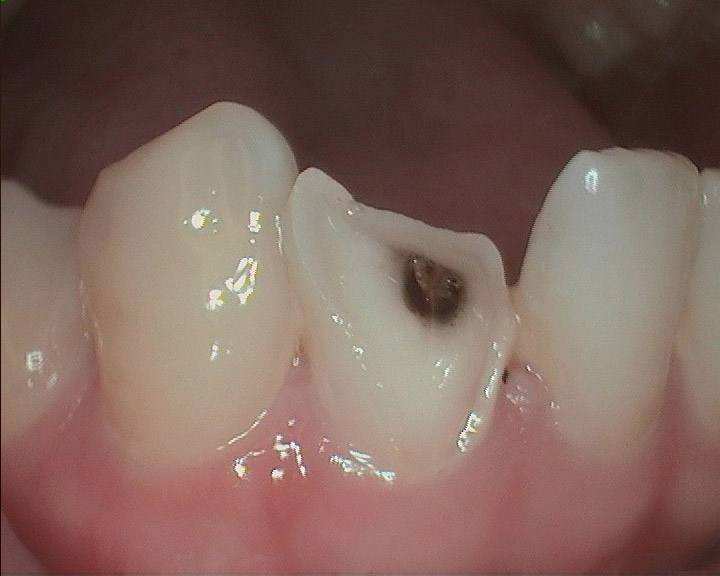

Trauma Case.

The patient had an accident and broke her lower front tooth. We put the fragment back and it looks just as nothing happened.

Tooth Fragment.

For a regular dentist, this may take 2 -3 appointments to fix, more tooth structure loss due to crowning, and might cost thousands of dollars. However, with Dr. Tao's expertise, such problems can be easily fixed with accuracy and high-quality in as little as one day.